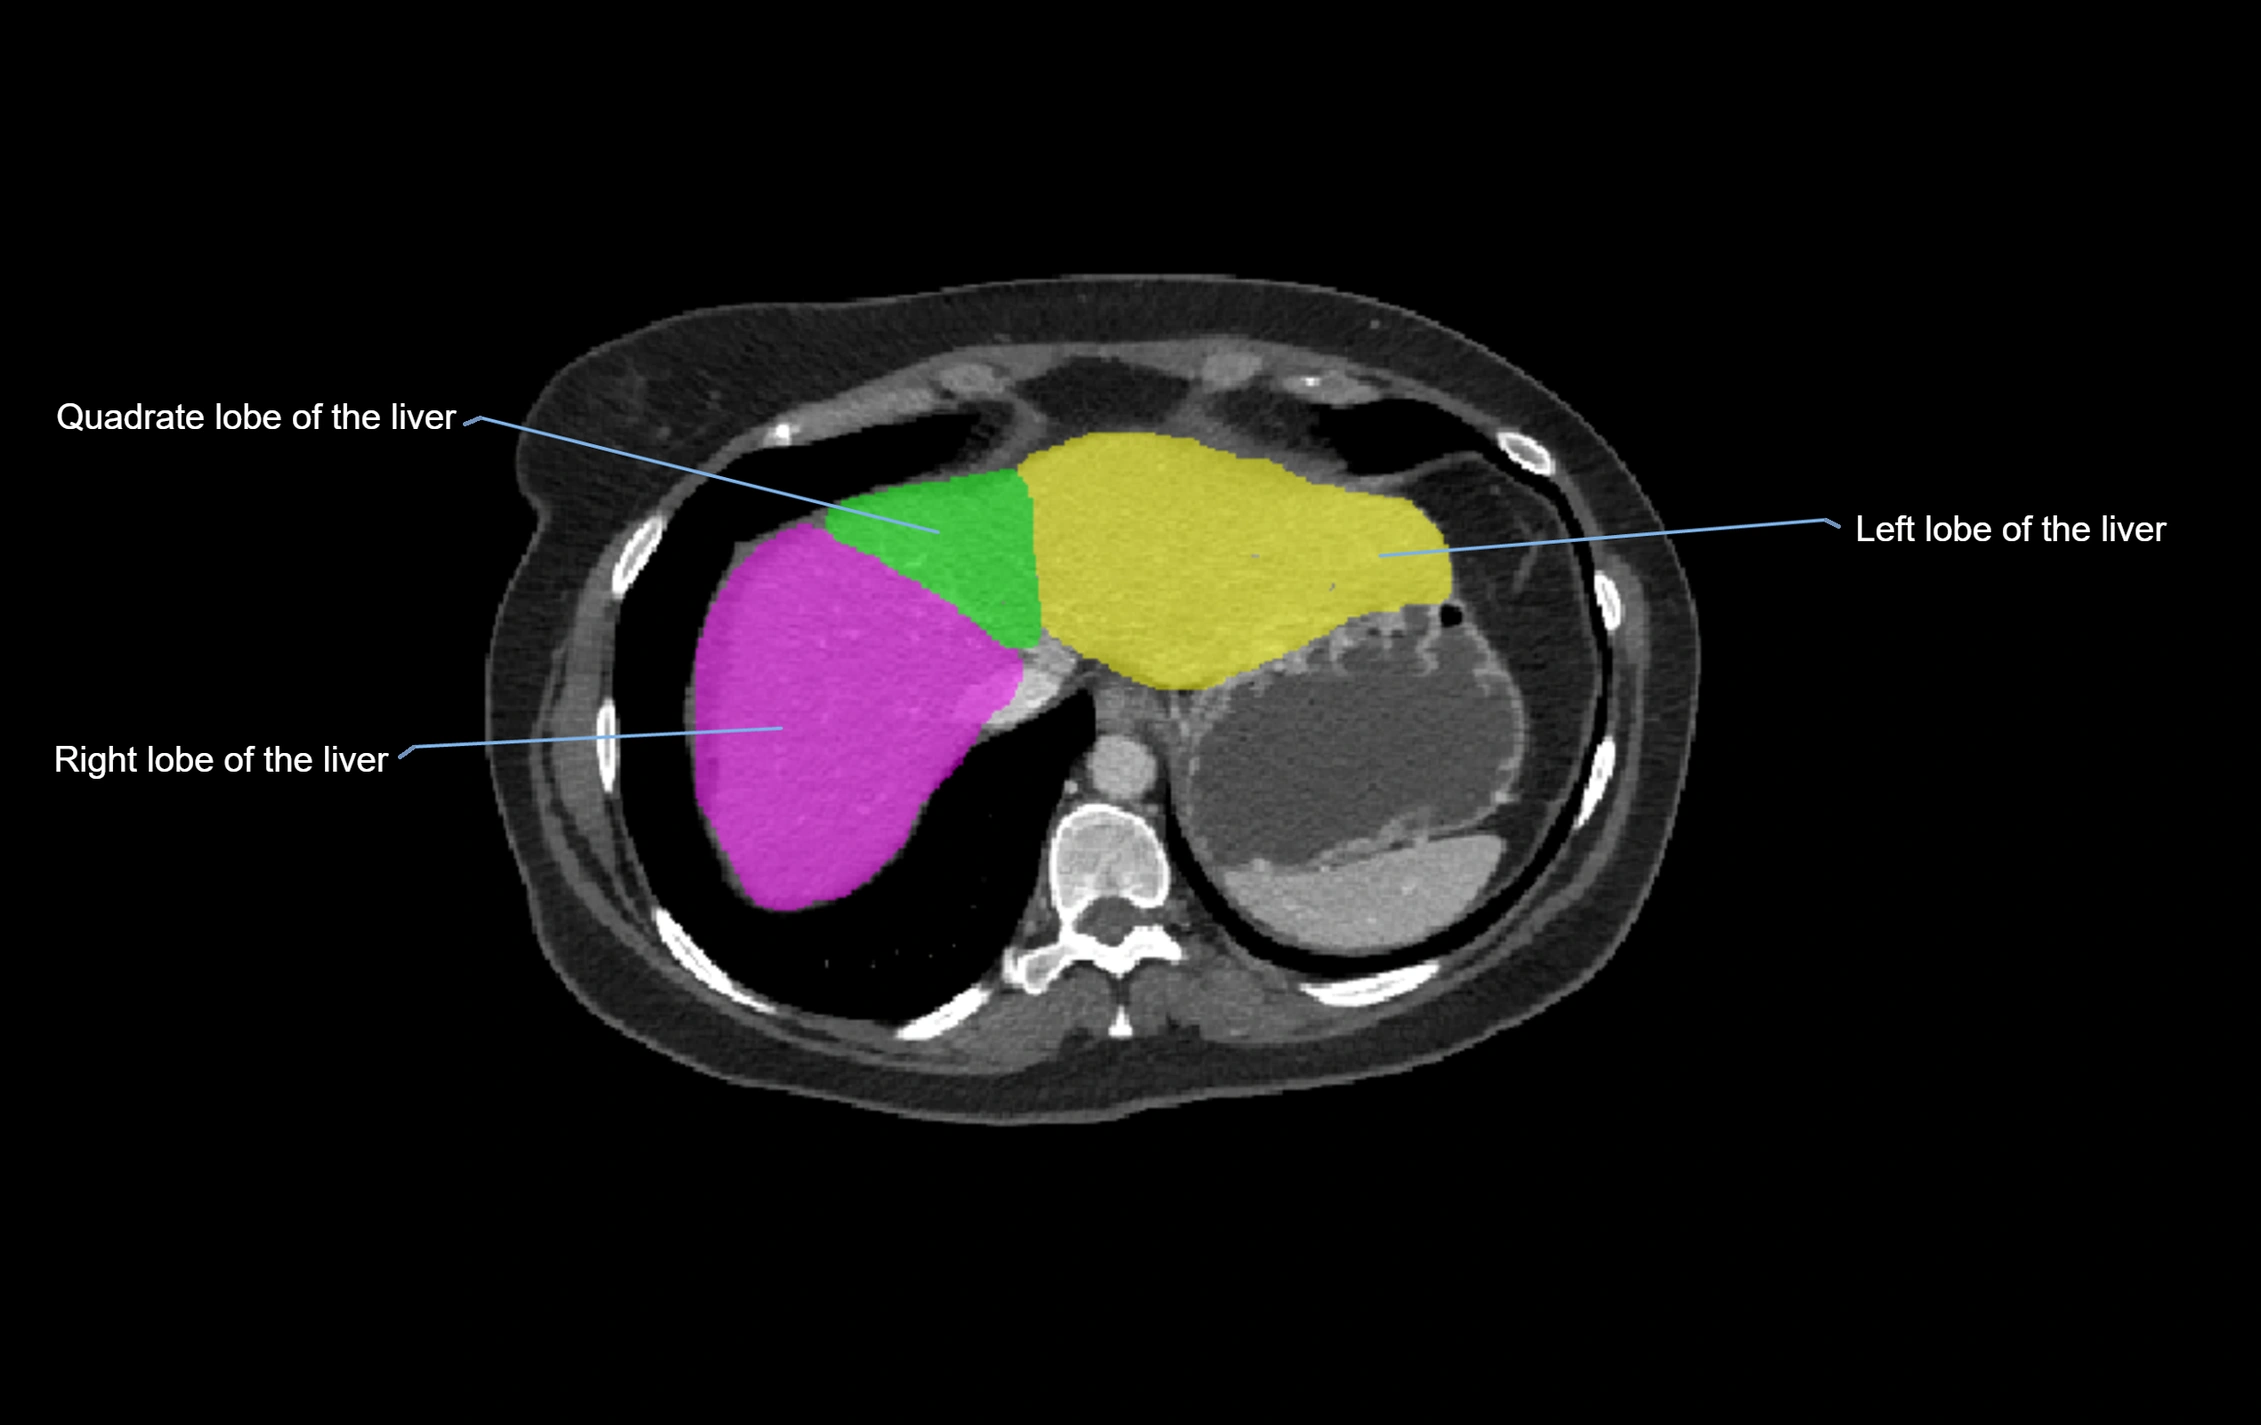

CT Image

image